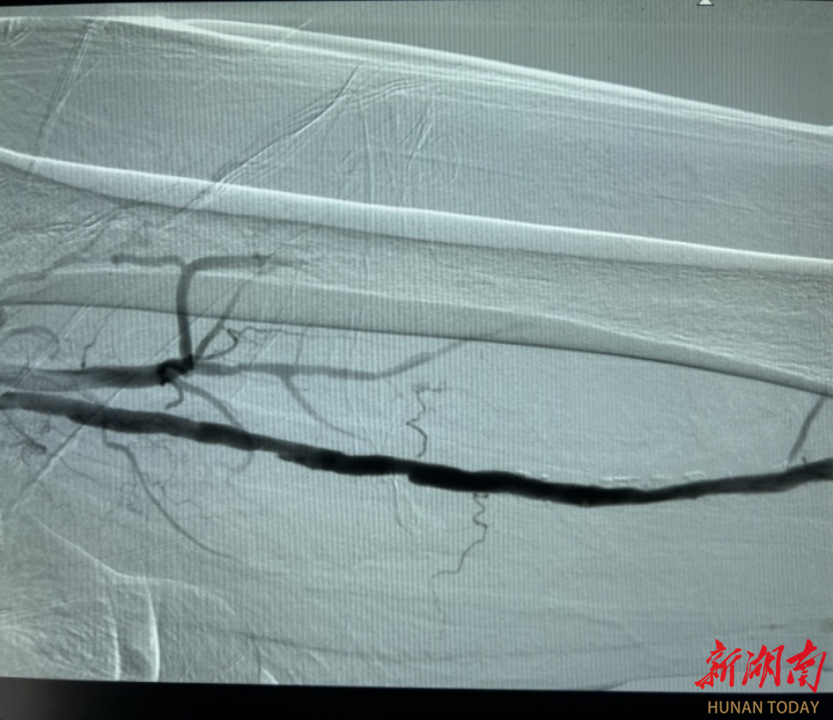

术前、术后造影对比图

手术当天,紧张的气氛弥漫在手术室。医生们通过股动脉穿刺,小心翼翼地将栓塞保护伞导入腘动脉,这一“保护伞”如同忠诚的卫士,准备兜住旋切过程中脱落的小斑块。在左股动脉中断,斑块旋切术正式开始。手术器械如同微型“刨子”,在直径仅几毫米的血管腔内辗转腾挪。医务人员凭借着精湛的技术,多次调整不同方向进行旋切刨吸。每一次切割都犹如在钢丝上行走,切得太薄无法达到治疗效果,切得太厚则可能损伤脆弱的血管。经过近两个小时的艰苦奋战,手术团队终于成功地将斑块切除并取出,随后药物球囊顺利扩张狭窄血管,抑制内膜增生,确保下肢动脉血流畅通。